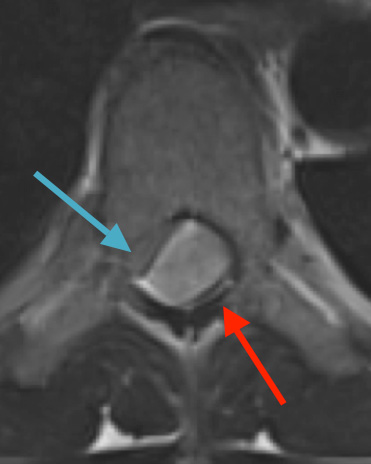

Preoperative MRI T1w demonstrating a large enhancing tumor (red arrow) causing severe cord compression and displacement (blue arrow)

Preoperative MRI T2 demonstrating obstruction of CSF around the cord (blue arrow), resulting from the tumor (red arrow)

Preoperative MRI T1w demonstrating a large enhancing tumor with severe cord compression